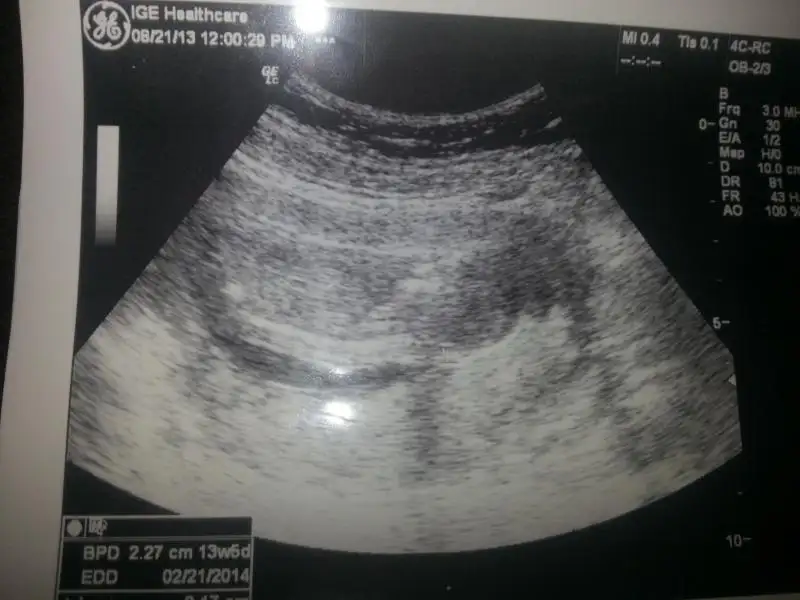

Eki Görüntüle 784338

Eki Görüntüle 784339 kızlar sonunda düzgün eklemeyi başardım yorumlarınızı bekliyorumbu arada 13 haftalıktı bebeğim bu ultrason görüntüsünde ama doktorum 16 haftadan önce söylemiyoruz dedi ben de ısrar etmedim